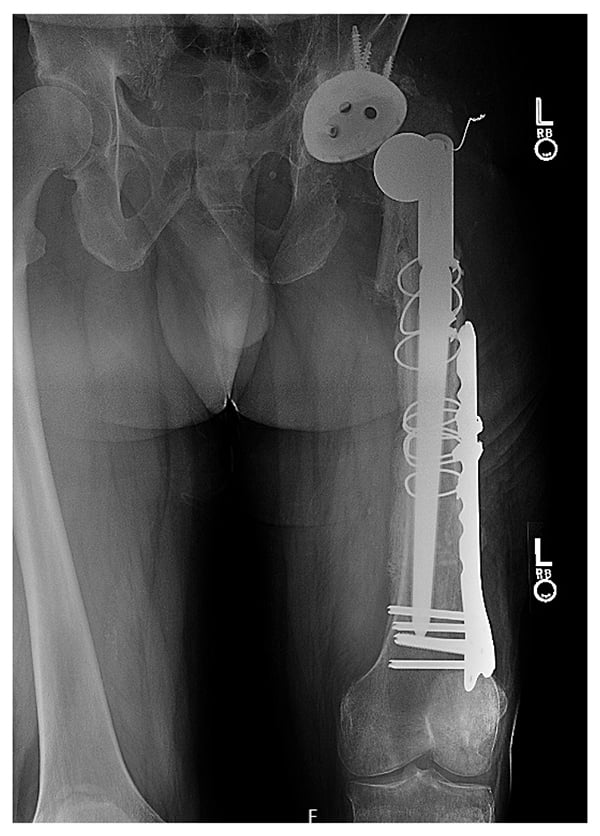

Assessment found a 4-in. leg length discrepancy, limited hip flexion to 60°, and pain and an audible clunk. Radiographs showed a revision construct with a multi-hole acetabular component fixed with multiple screws and a modular tapered stem with cerclage wires that had subsided (Fig. 1). Notably evident was a proximal femur fracture, joint dislocation, and an aggressive periosteal reaction along the diaphysis and distal metaphysis of the femur, which raised concerns for underlying osteomyelitis. With regular monitoring, antibiotic and antifungal therapies were stopped for 2 weeks, and hip aspiration was positive for Corynebacterium and Candida albicans. Due to the polymicrobial culture results and involvement of most of the femur, an explant of the revision hip replacement, resection of the distal femur, and insertion of a total femoral replacement spacer were planned.

An extensile posterolateral approach and separate midline approach to the left knee were performed with 2 surgical teams simultaneously. All components were safely removed, the proximal tibia was cut, and the patella was debrided. A distal femoral component (Stryker GMRS) was implanted and coated with high viscosity cement (Palacos R+G) containing gentamicin 0.5 g, vancomycin 2 g, and voriconazole 400 mg per bag (Fig. 2). To maximize hip stability due to posterior-wall bone loss, a 64-mm bipolar head was used (Fig. 3). Deep surgical drains were placed, and negative pressure dressings were applied to the incisions.

Figure 2

Figure 2: Intraoperative photo shows a total femoral component coated with polymethylmethacrylate cement containing antibiotics and antifungals.

Figure 3

Figure 3: Postoperative radiograph demonstrates the total femoral component spacer and large bipolar head articulating with the acetabulum.

Postoperatively, the leg length discrepancy had improved, with the external shoe lift decreased from 4 in. to 1.5 in. The patient was hospitalized for 2 weeks for treatment with IV vancomycin, piperacillin, and caspofungin; after 6 weeks he transitioned to oral doxycycline and fluconazole. After 4 months, he began weight bearing with crutches, but at 6 months he noticed persistent groin pain. Radiographs (not shown) raised concerns for possible acetabular erosion secondary to the bipolar head. He was placed on a 2-month antimicrobial holiday, with blood and aspiration samples indicating no infection.